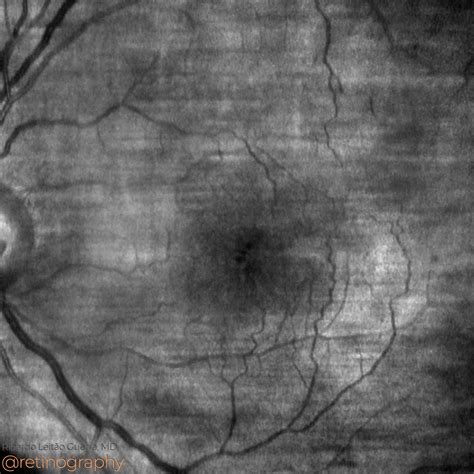

Vision is one of our most precious senses, yet it is often taken for granted until a complication arises. One such complication that can significantly impact your central vision is Cystoid Macular Edema (CME). This condition occurs when fluid accumulates within the layers of the macula, the small, central part of the retina responsible for sharp, detailed vision. When this happens, the macula swells, leading to blurred or distorted vision. Understanding what causes this condition, how it manifests, and the available treatment paths is essential for anyone dealing with retinal health concerns.

Cystoid Macular Edema is not a disease in itself but rather a sign of an underlying issue. The term "cystoid" refers to the cyst-like spaces that form as fluid collects in the macula, while "edema" simply means swelling. Because the macula is critical for tasks like reading, driving, and recognizing faces, any interference in this area can cause noticeable changes in your sight. If left untreated, the chronic swelling can lead to permanent damage to the retinal cells, making early intervention vital.

To confirm the presence of CME, an ophthalmologist will perform a comprehensive eye exam. Standard tests include a dilated fundus examination, where the doctor looks at the back of the eye. More precise imaging is often used to visualize the fluid:

Fluorescein Angiography (FA) Uses a special dye to track blood flow and highlight leaking vessels.